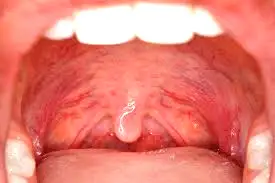

لوزه سوم یا آدنوئید یکی از بخشهای مهم سیستم دفاعی بدن کودکان است که در پشت بینی و بالای گلو قرار دارد. وجود لوزه سوم در سالهای ابتدایی زندگی کاملاً طبیعی است و به بدن کمک میکند با میکروبها مقابله کند، اما در برخی کودکان این بافت بیش از حد بزرگ میشود و مشکلاتی در تنفس، خواب و حتی رشد فکها و دندانها ایجاد میکند.

لوزه سوم یا آدنوئید یک بافت لنفاوی است که مانند فیلتر عمل میکند و جلوی ورود میکروبها به بدن را میگیرد.

این بافت معمولاً از بدو تولد وجود دارد و بین ۳ تا ۷ سالگی به بیشترین اندازه خود میرسد. سپس بهتدریج کوچک میشود و در دوران نوجوانی تقریباً از بین میرود.